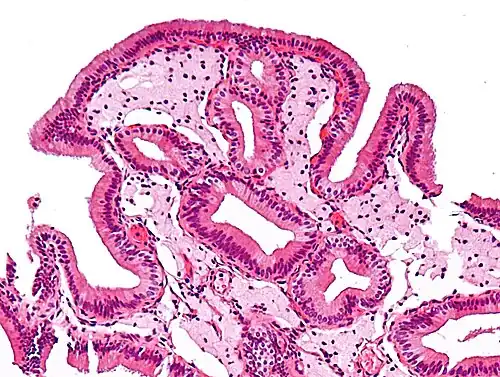

The name strawberry gallbladder comes from the typically stippled appearance of the mucosal surface on gross examination, which resembles a strawberry. The term was coined by surgical pathologist William C. MacCarty of the Mayo Clinic in 1910.[2] Cholesterolosis results from abnormal deposits of cholesterol esters in macrophages within the lamina propria (foam cells) and in mucosal epithelium. The gallbladder may be affected in a patchy localized form or in a diffuse form. The diffuse form macroscopically appears as a bright red mucosa with yellow mottling (due to lipid), hence the term strawberry gallbladder. It is not tied to cholelithiasis (gallstones) or cholecystitis (inflammation of the gallbladder).[3]

Micrograph of cholesterolosis of the gallbladder